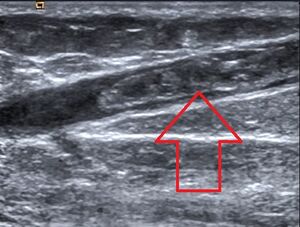

جلطات الدم